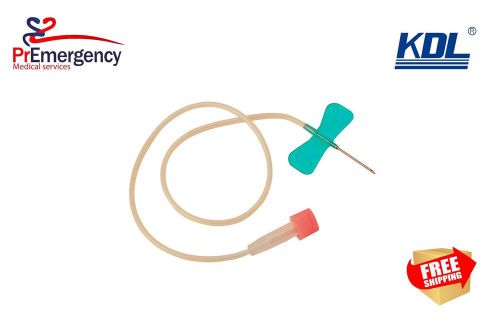

Disposable 21G Butterfly Needle Scalp Vein